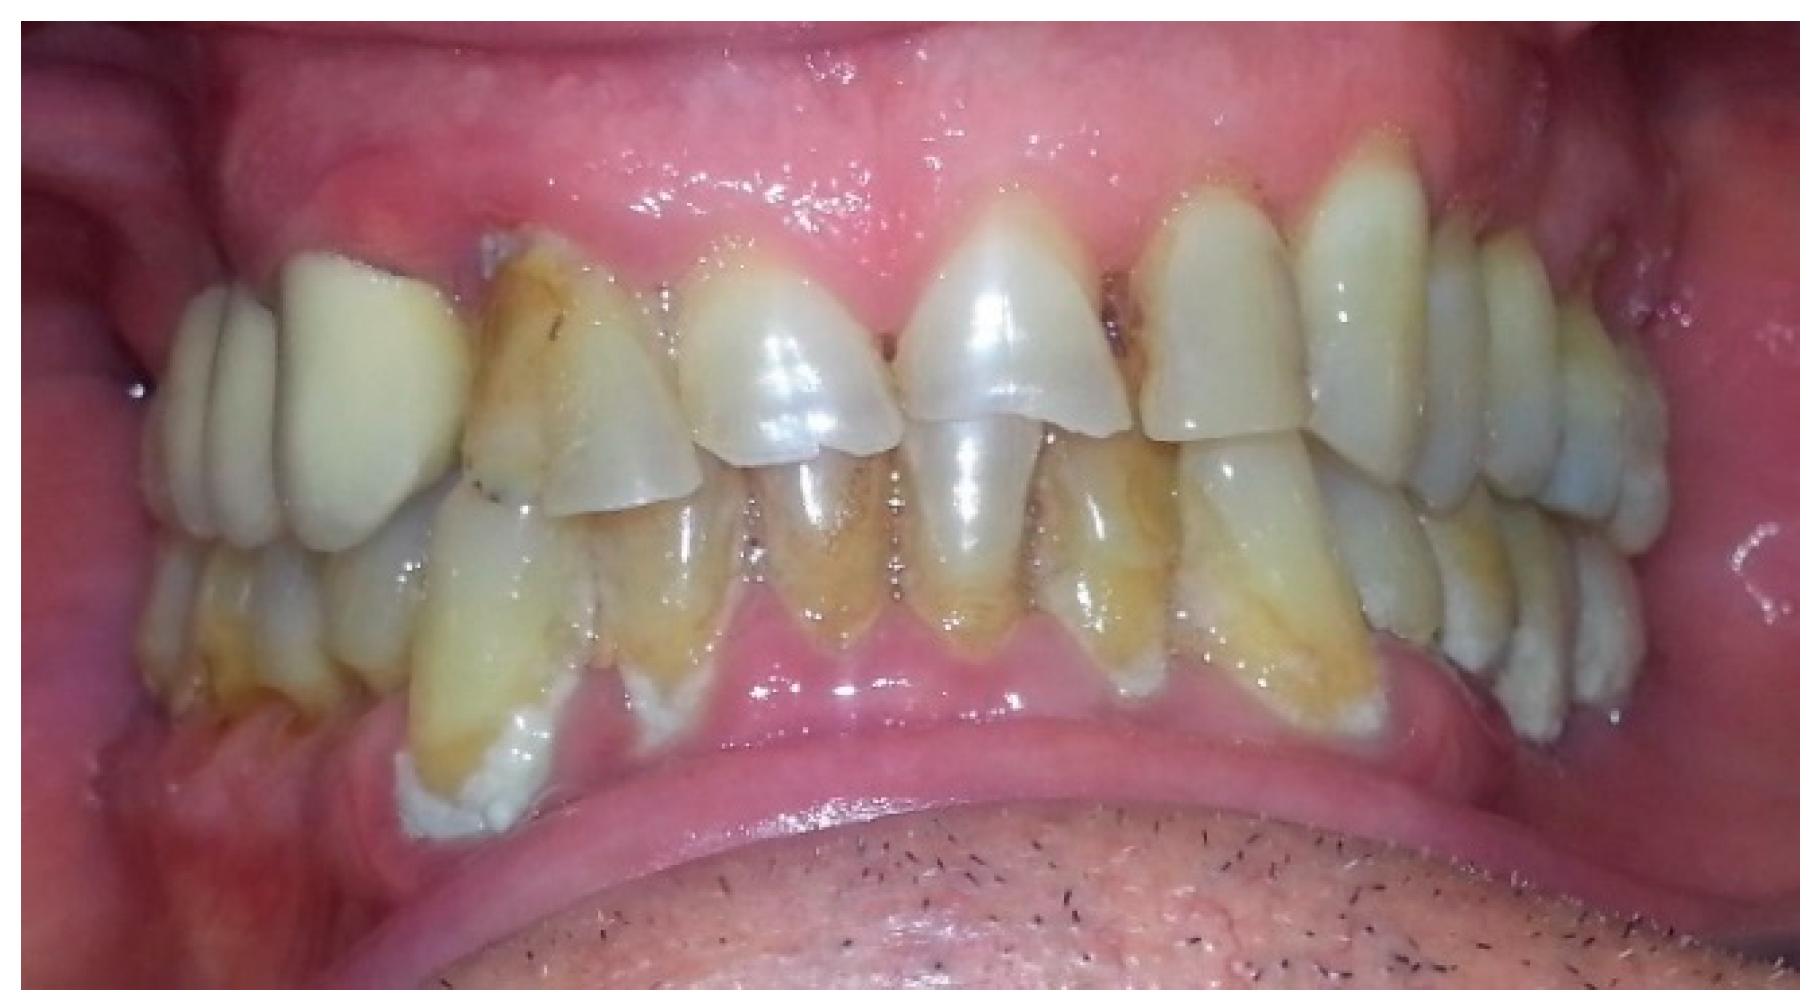

4. Case Report